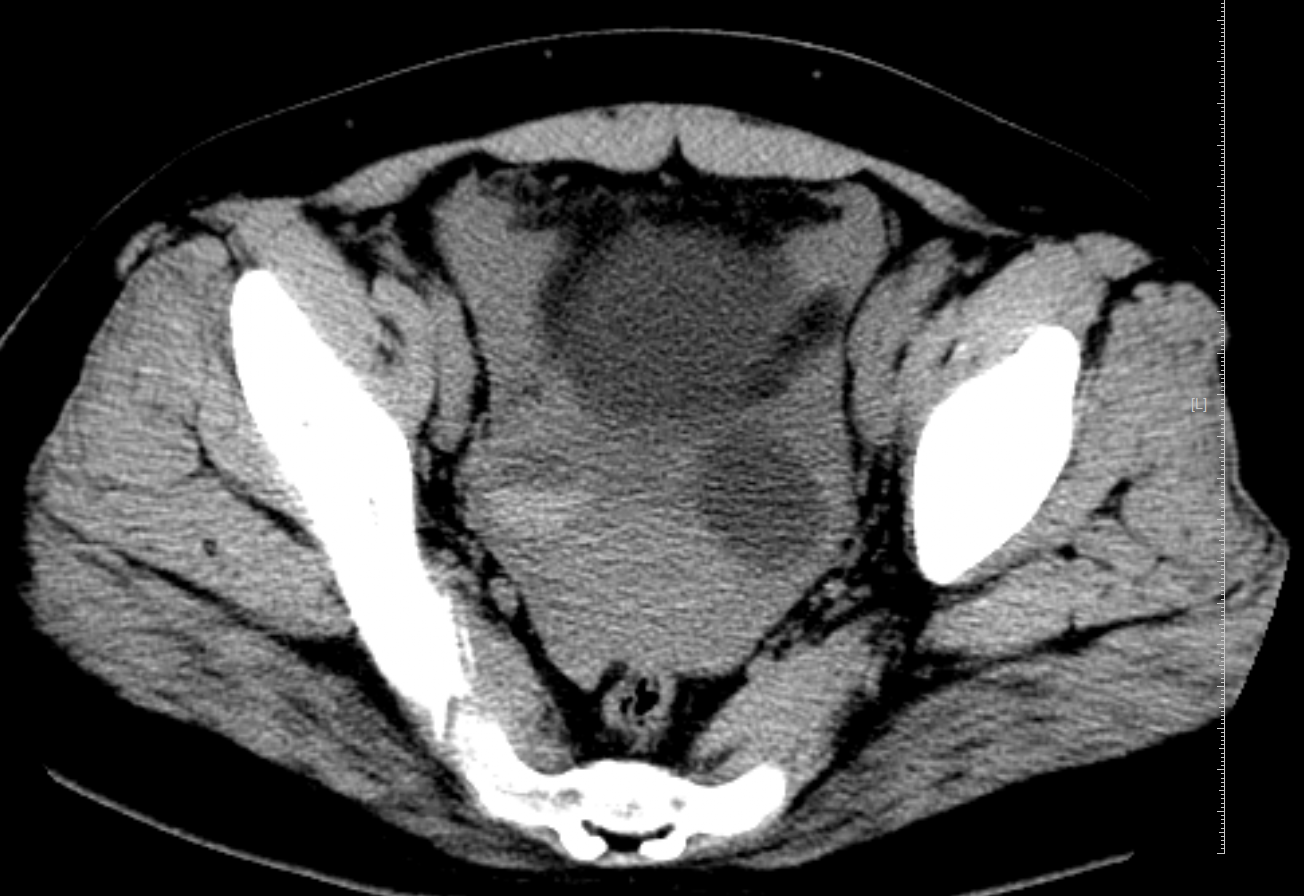

近日,一位14岁体型偏肥胖的女生,因腹痛来我院放射科行CT检查,CT提示双侧附件区囊肿,盆腔积血,放射科诊断医生阅片后考虑卵巢黄体囊肿破裂,而后的手术也证实了这一诊断。

黄体囊肿破裂-盆腔积血